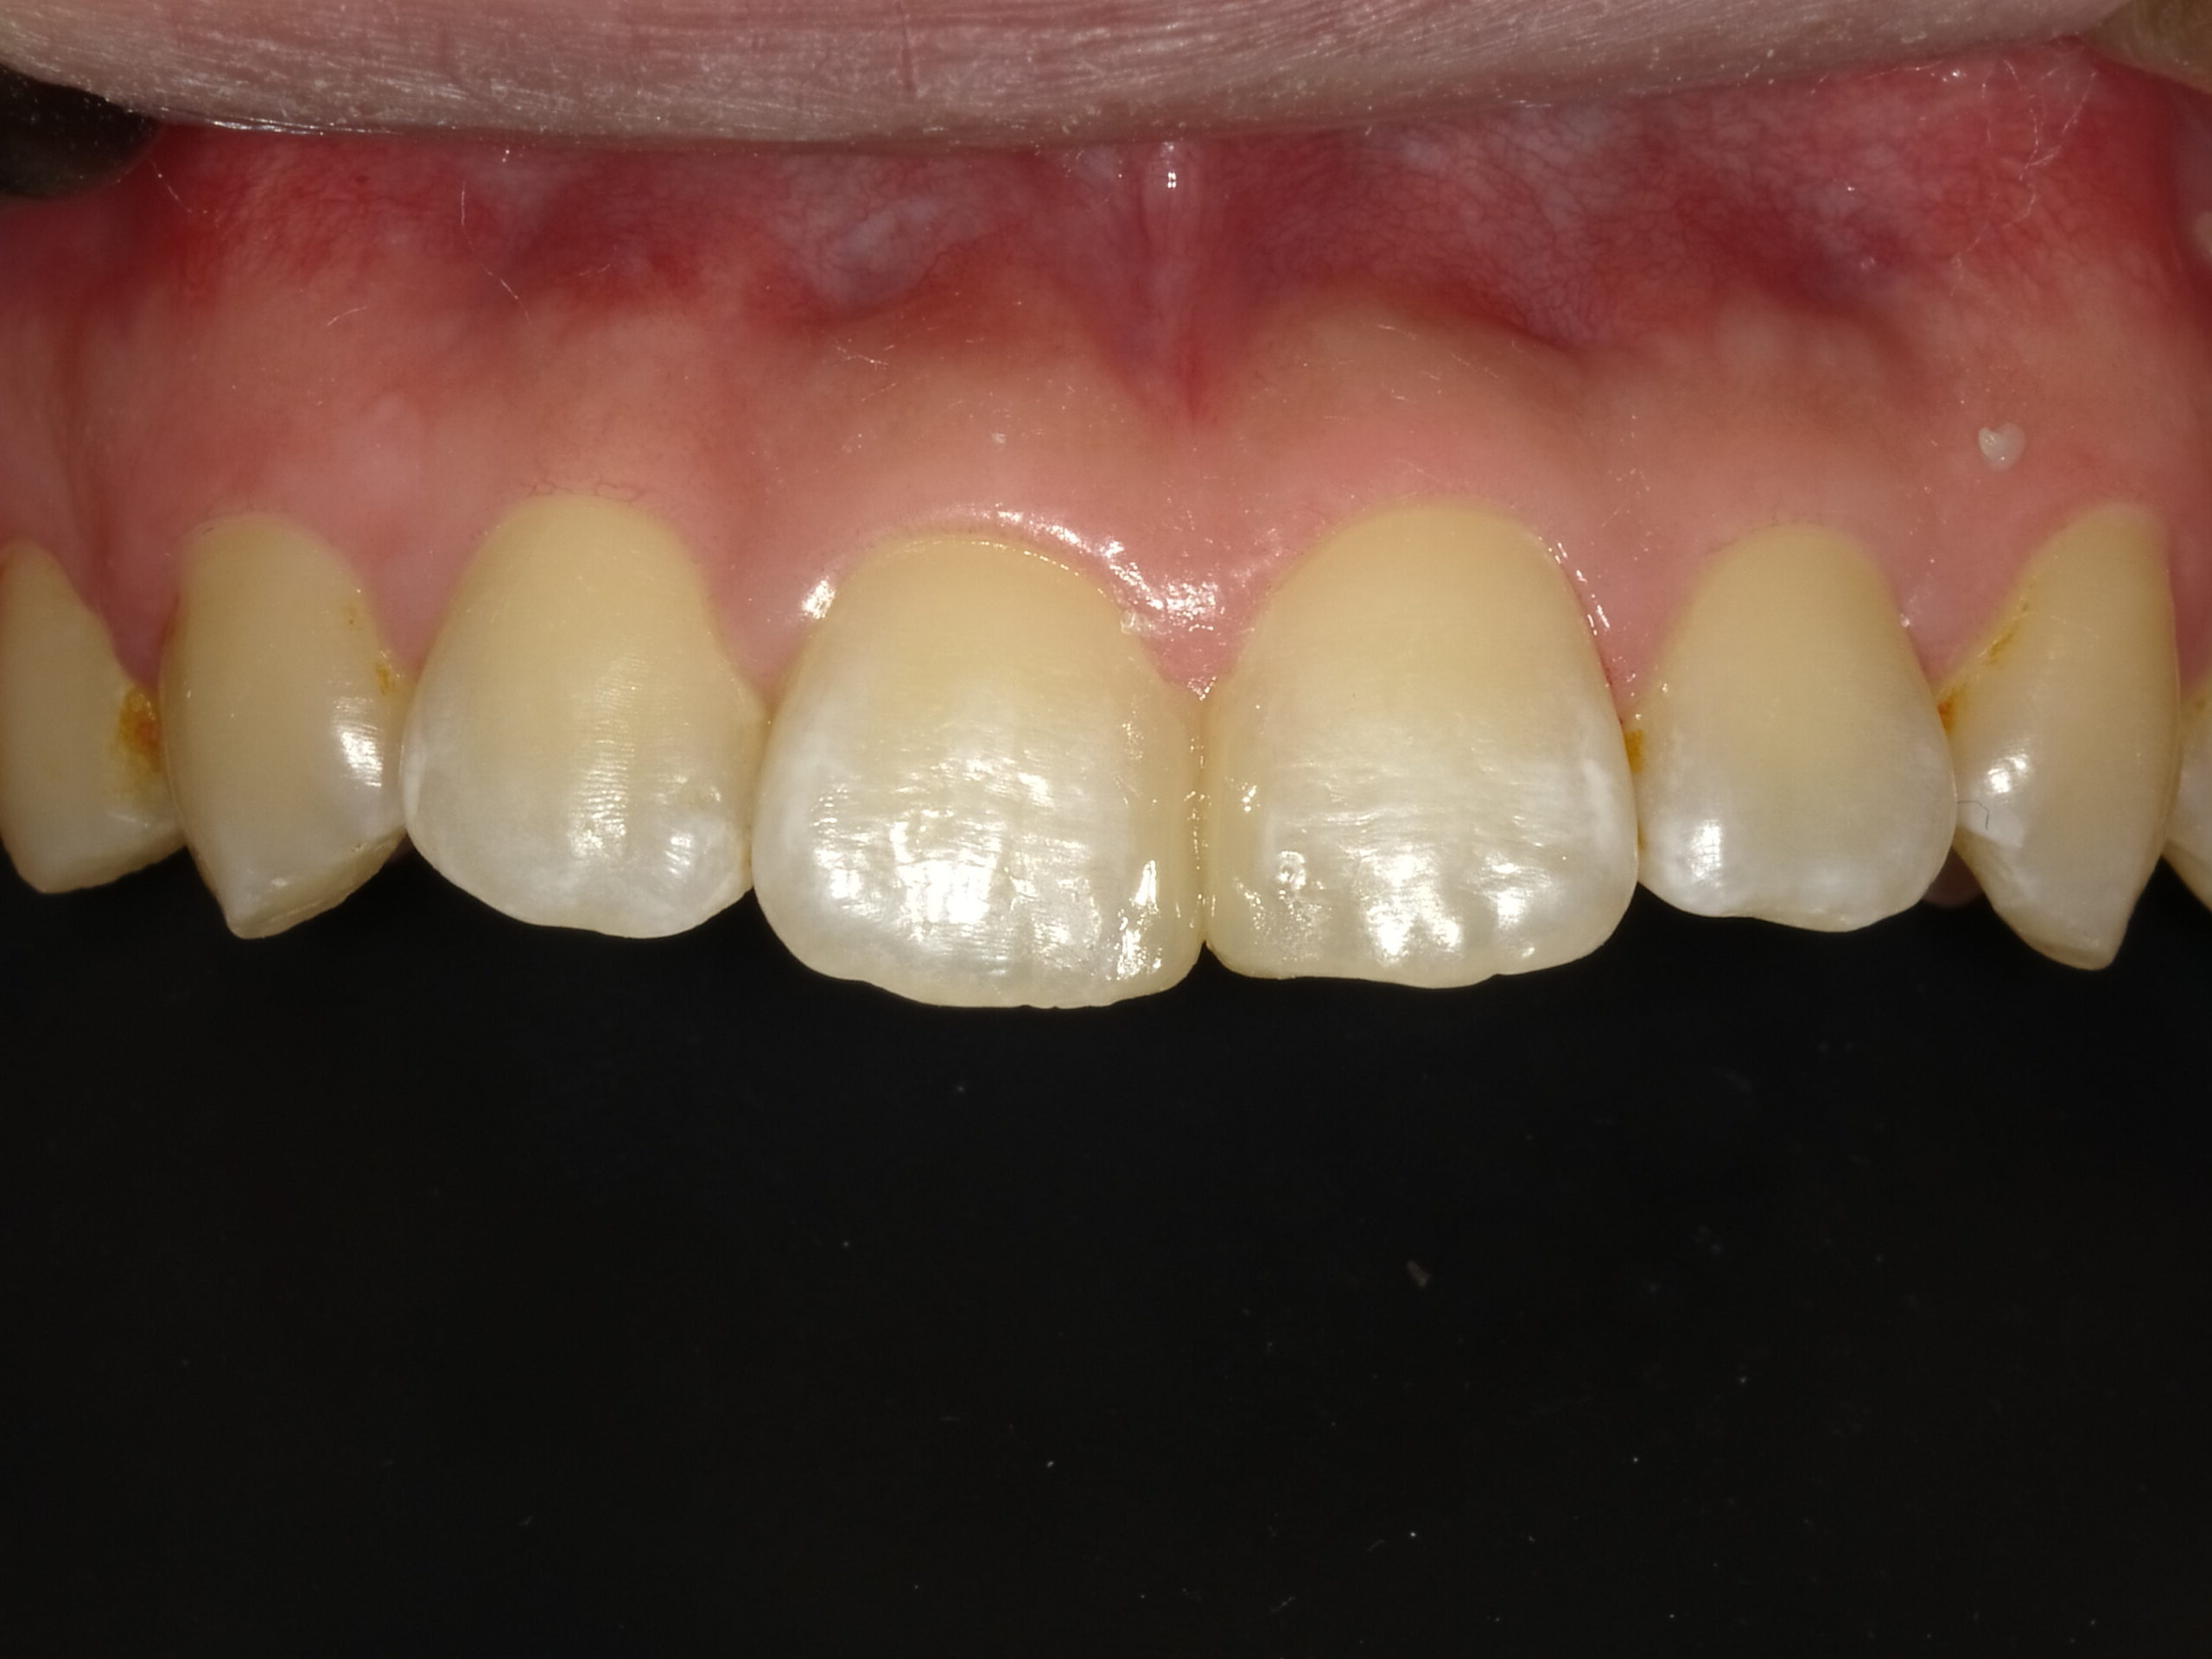

審美歯科esthetic